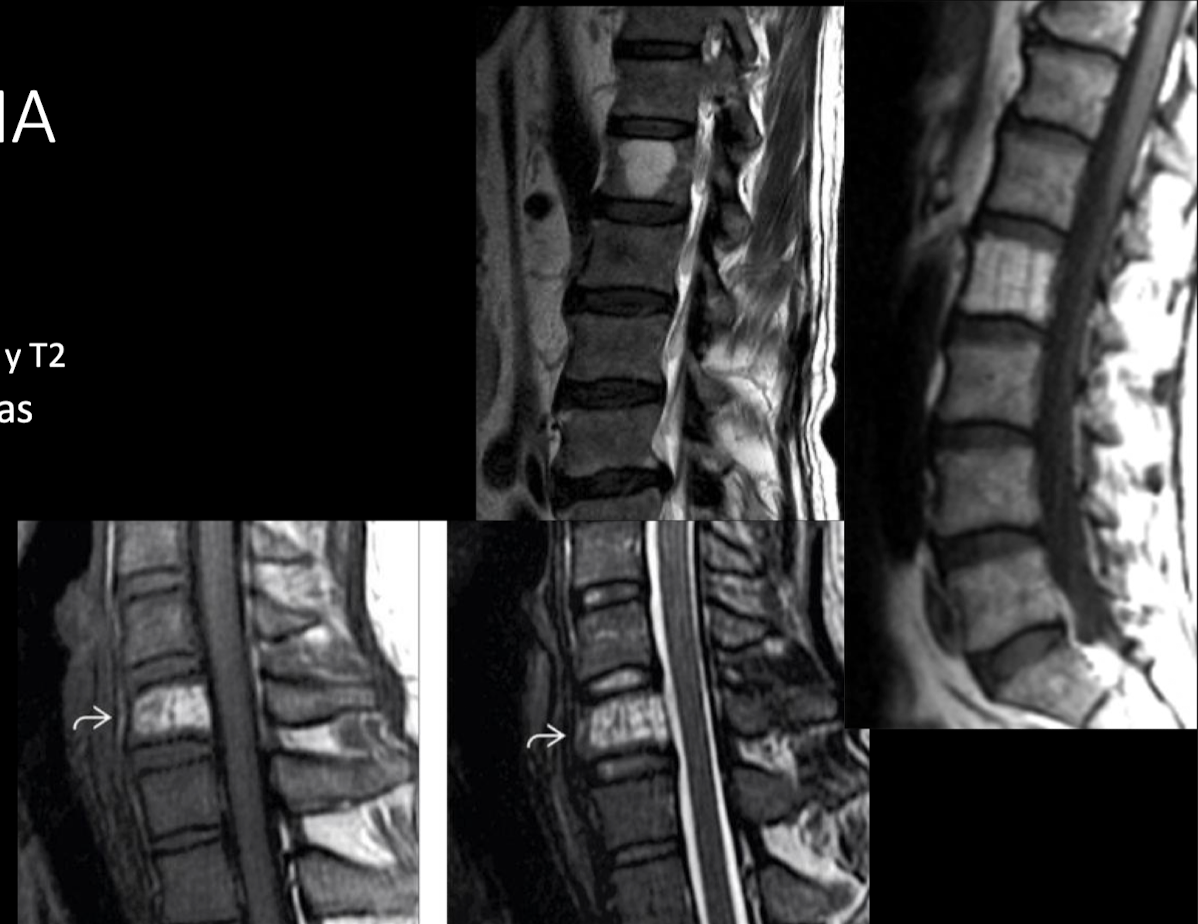

RM

A

LO MEJOR hiperintensos T1T2

detect pequeños hemangiomas

extensión extraósea

capta contraste